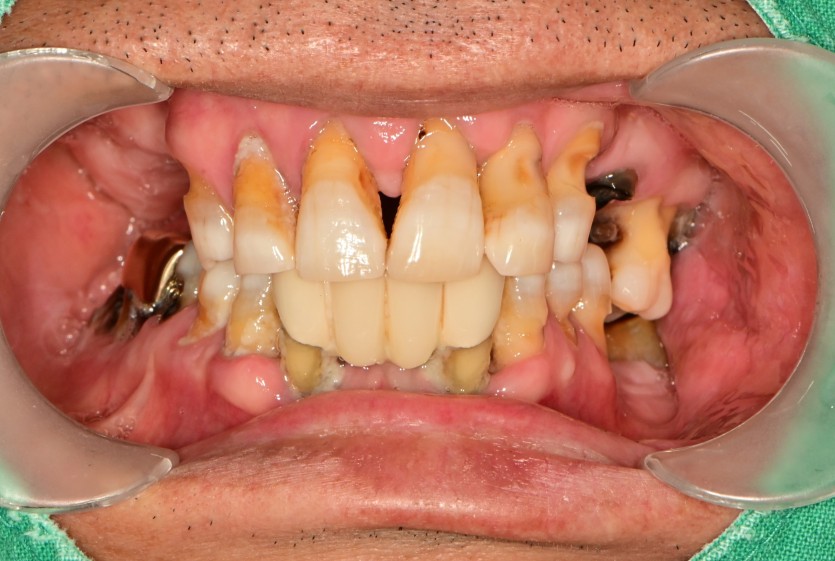

전체 임플란트 증례입니다.

17개의 임플란트로 완성하였습니다.